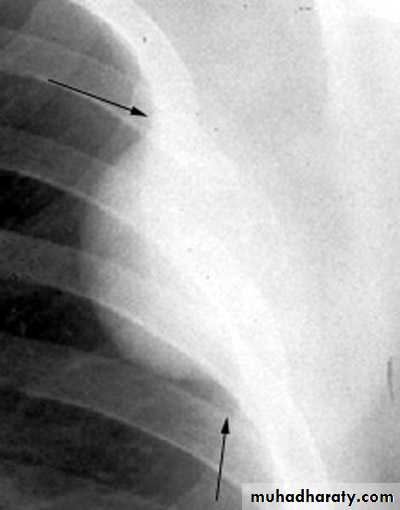

Encysted peural effusion

Sub costalFissural

Sub pulmonary